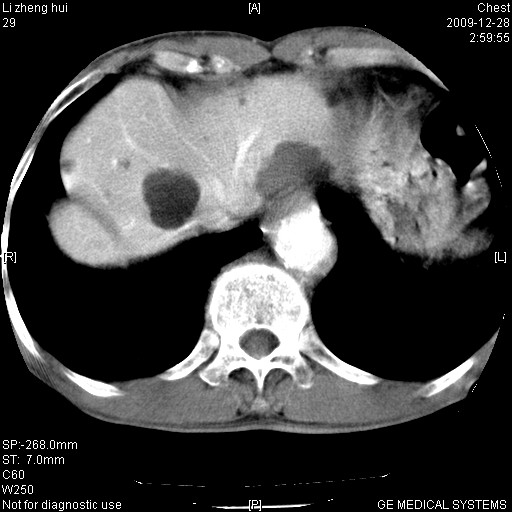

男  79岁 胸部痛急诊入院,晚上做的增强

支持,另有肝囊肿。

1)考虑胸主动脉壁间血肿或夹层动脉瘤。2)多发性肝囊肿。

1)考虑胸主动脉附壁血栓或夹层动脉瘤。2)多发性肝囊肿。

支持,另有肝囊肿